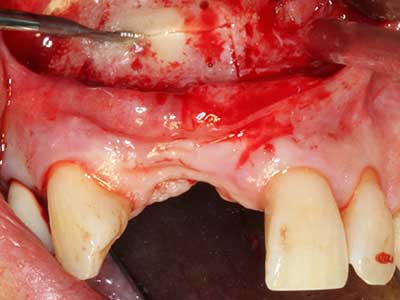

Il tessuto osseo non è semplicemente una struttura minerale, ma contiene anche una percentuale significativa di fibre di collagene. Ciò significa che non possiede solo una buona forza di compressione, ma anche un certo livello di flessibilità che è possibile sfruttare durante l'esecuzione degli accrescimenti di osso. Nella procedura di espansione classica con incisione ossea, la cresta alveolare atrofizzata viene incisa longitudinalmente ed espansa con cautela dopo aver raggiunto una profondità di osteotomia adeguata (figg. 13-16), idealmente senza una sostanziale rimozione del periostio (Brugnami, Caiazzo et al. 2014, Stricker, Fleiner et al. 2014). I sistemi a piastra e vite con distanza di espansione incrementale si sono dimostrati efficaci nella separazione delle due lamelle ossee restando al di sotto della soglia di frattura. In generale, sono richieste larghezze dell'osso residuo di almeno 3-4 mm (Chiapasco, Zaniboni et al. 2006) per garantire un'adeguata flessibilità e una copertura sufficiente dell'osso per gli impianti futuri. Se necessario, un'osteotomia di rilascio verticale su uno o più lati può migliorare la flessibilità. Una combinazione con ulteriori tecniche di accrescimento, in particolare dal lato buccale, è stata descritta come un'alternativa alla tecnica classica.

La procedura di incisione è particolarmente atraumatica e non comporta una perdita significativa di dimensione durante l'utilizzo delle seghe piezoelettriche, così come non si notano differenze rilevanti tra impianti in mandibole incise e impianti in una cresta alveolare senza deficit osseo (Chiapasco, Zaniboni et al. 2006, Danza, Guidi et al. 2009). Una sufficiente irrigazione continua è essenziale, tuttavia, in particolare con incisione profonda e localmente ristretta, per prevenire la sollecitazione termica nelle regioni apicali dell'osteotomia.